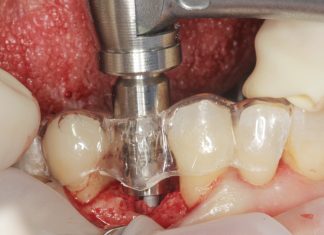

Il laser erbio in chirurgia ossea orale Premium

Il laser erbio è uno strumento versatile, che offre un'ampia possibilità terapeutica con l'applicazione sui tessuti duri e molli. A livello ambulatoriale può essere utilizzato per trattare diverse condizioni cliniche e come alternativa efficace agli strumenti meccanici tradizionali per eseguire interventi di chirurgia orale, offrendo precisione con ridotto danno termico e rapidità di guarigione. Gli autori presentano quattro casi clinici dove il successo terapeutico è stato ottenuto grazie all'impiego del laser erbio.